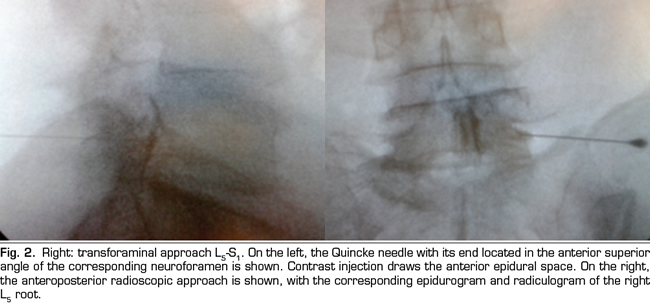

The final position of the needle in the oblique view was the subpedicular zone, while in the lateral view was the anterior superior angle or the roof of the neuroforamen, in the so-called safety triangle (Figure 2). The contrast volume injected was equivalent to the performed in the interlaminar group, obtaining a radiculogram and epidurogram after the injection (Figure 2). The solution of betamethasone was the same used in the interlaminar group, injecting the total volume of the solution in one or two levels, depending on clinical criteria.